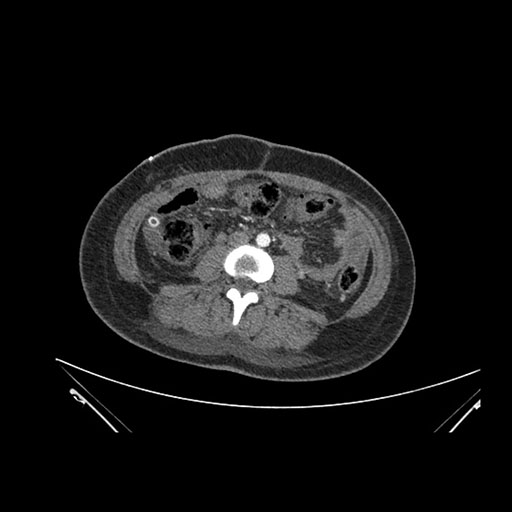

Imaging Analysis

Look through the patient's CT scan to identify any areas of concern for the necessary procedure.

Axial Venous

Based on initial findings, which issue(s) would you be most concerned about?